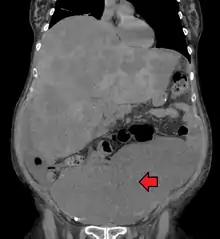

Medical imaging

A colorectal cancer is sometimes initially discovered on CT scan.[79]

Presence of metastases is determined by a CT scan of the chest, abdomen and pelvis.[20] Other potential imaging tests such as PET and MRI may be used in certain cases.[20] MRI is particularly useful to determine local stage of the tumor and to plan the optimal surgical approach.[79]